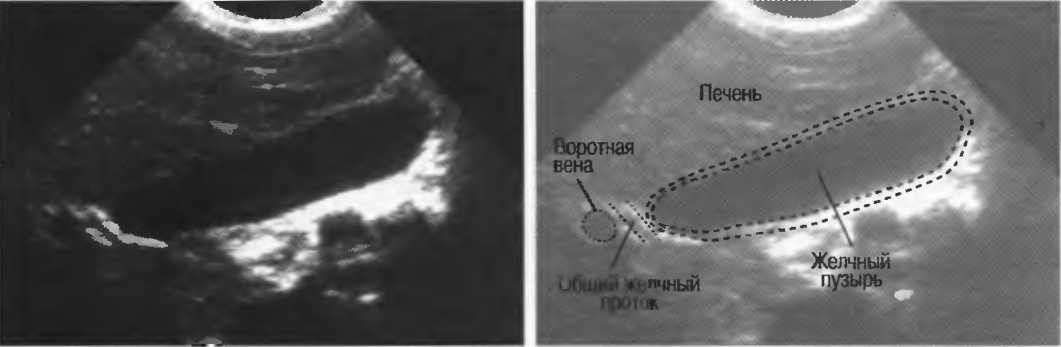

Рис. 10а. Жидкостьсодержащая структура — желчный пузырь, с задним усилением, имеющим место в результате низкого уровня затухания звукового сигнала в жидкости. Стенки желчного пузыря дают две боковые тени.

Акустическое усиление и акустическая тень

Чистые жидкости проводят ультразвуковой сигнал без существенного ослабления, поэтому отраженные эхосигналы, идущие от тканей, расположенных за жидкостью, обычно усилены (более яркие). Этот феномен известен как «акустическое усиление» (рис. 10а). Прием достаточного количества жидкости для заполнения желудка дает смещение кишечника, содержащего газ, и тем самым создает акустическое окно. Это особенно полезно для визуализации тела и хвоста поджелудочной железы.